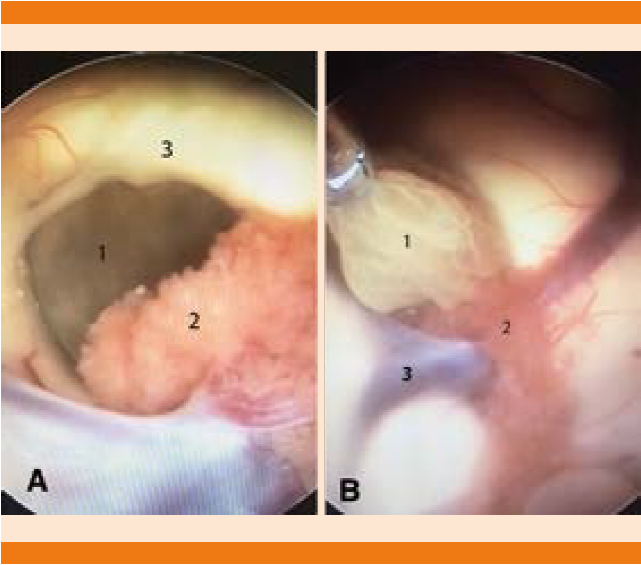

La tomografía de cráneo simple y con contraste evidenció hidrocefalia aguda no comunicante y edema cerebral. Se procedió a colocación de válvula de derivación ventrículo-peritoneal, sin complicaciones con control tomográfico posterior donde se observó válvula de derivación ventrículo-peritoneal en el asta anterior del ventrículo derecho. Los estudios de imagen se complementaron con una resonancia magnética de cráneo en secuencia FIESTA (Figura 1) donde ese observó un quiste intraventricular anterior a la masa intertalámica con nódulo en su interior (escólex) y pared delgada bien definida, con lo que se estableció el diagnóstico de neurocisticercosis intraventricular. La paciente se sometió a una neuroendoscopia para extracción del quiste (Figuras 2 y 3). El procedimiento se realizó sin complicaciones y durante el quinto día de hospitalización se inició tratamiento con albendazol a dosis de 15 mg/kg/día y esteroides. La paciente tuvo buena evolución clínica, con mejoría del estado de alerta, persistencia de inatención y con alteración de la memoria de trabajo; el resto de la exploración neurológica fue normal.

Figura 2 Imágenes de la neuroendoscopia: A. Se observa el foramen de Monro y en el interior se observa el cisticerco (1). Los puntos anatómicos de referencia son el plexo coroides (2) y el pilar anterior del fórnix (3) para delimitar el foramen. B. Imagen de la extracción del quiste: (1) cisticerco extraído cuidadosamente con una pinza de biopsia para conservar la integridad de la cápsula y evitar una reacción inflamatoria. (2) Plexo coroides. (3) Vena tálamo estriada.

Los quistes ventriculares pueden tratarse quirúrgicamente o con tratamiento cisticida, según su tamaño y localización; sin embargo, las guías se inclinan al tratamiento quirúrgico con escisión directa o aspiración por neuroendoscopia con fenestración del tercer ventrículo. La neuroendoscopia es un procedimiento que en los últimos años ha experimentado avances en equipo y en habilidades; aunque la bibliografía aún es escasa, la resección neuroendoscópica con ventriculostomía del quiste es el tratamiento de elección, porque se trata de una intervención de mínima invasión, tiene pocas complicaciones, implica menor hospitalización y menores costos.1,7,10,16-18